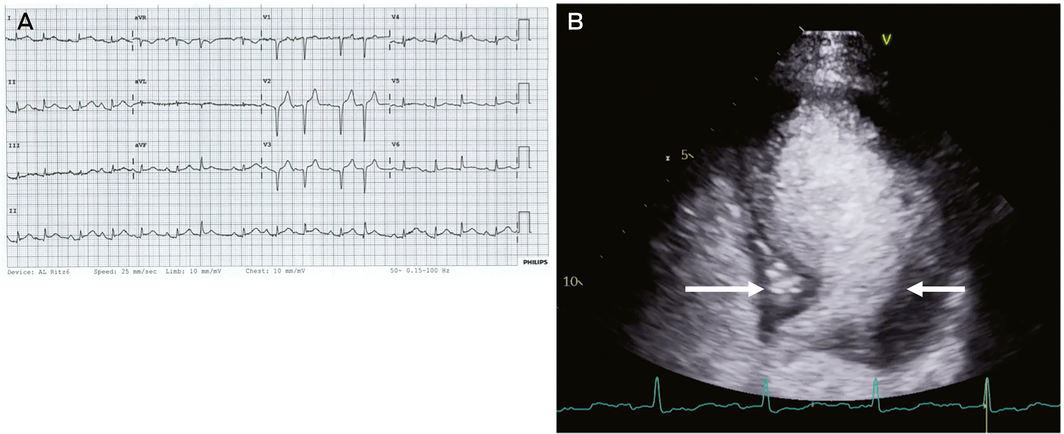

A 71‐year‐old woman presented to the emergency department complaining of chest pain. On arrival, an ECG demonstrated diffuse ST elevation (Box) and troponin was elevated (7800 ng/L). Coronary angiography was performed immediately which did not demonstrate any obstructive lesion and she was admitted to the intensive care unit (ICU) for ongoing haemodynamic support. Echocardiography performed in the ICU showed a dilated left ventricle with an akinetic apex and preserved contraction of the basal segments (Box) suggestive of takotsubo cardiomyopathy. On questioning regarding recent stressors, our patient, who lived alone, reported significant anxiety about not being able to visit family due to social distancing, and was particularly saddened by being unable to see her grandchildren.